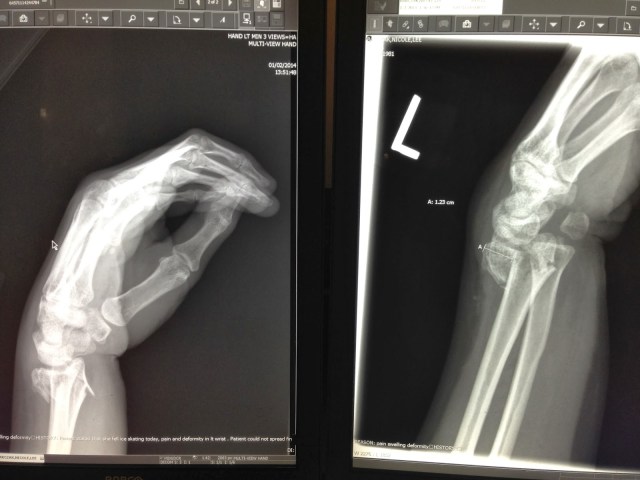

I sat down and started bawling. I didn’t want to move… my wrist hurt so bad. Someone convinced me to move my hand and look at it and it looked like it was in the shape of a “z” it was so disfigured. I knew it was bad. This made me panic more. The rest was such a blur… someone called my grandma, and the paramedics. They checked me out and said to head to the ER or ride in the ambulance. Syd had just got her drivers license so somehow I managed to arrange to have my grandma take the kids home in the van and Syd drive me to the ER in my grandmas car. Someone took my skates off and helped me get my boots on. It was all a blur and I was in so much pain, and crying a terrible ugly cry. I wanted someone to give me pain medication.

At the ER I had finally calmed down, and they were able to help me out of my coat without too much pain. They called my wrist a “positive deformity” HAHA! Sydney and I were there for awhile and they finally got me in for x-rays and into a room with an IV. They knocked me out and snapped my wrist back into place (somewhat) and I woke with a bandaged up arm. Ry showed up after his doctors appt. They took xrays again and said I’d likely need screws because the break was in the wrist joint and my bone was in 3 pieces. Great!! So, tomorrow I’ll have to call the orthopedic doctor and find out what is going on. I am so thankful Sydney was with us. She was such a huge help, and great support for me.